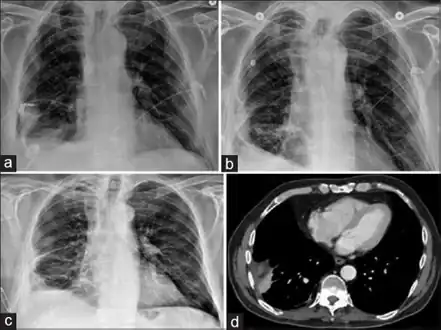

| Progression of empyema | |

Lungs

Empyema

Empyema with abscess